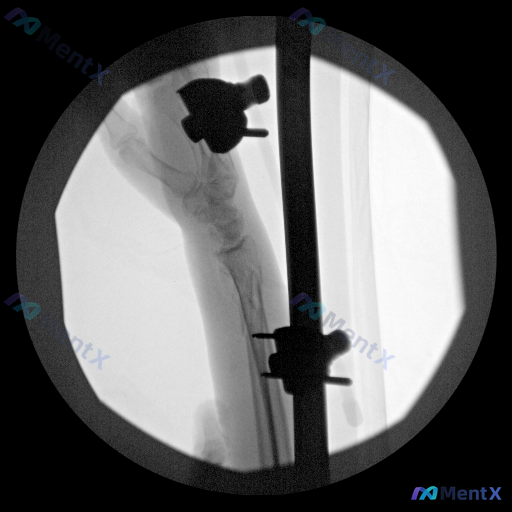

整理到一张前臂远端及腕关节的C型臂透视影像,背景是桡骨远端骨折外固定术后。 目前可见的表现包括: - 明确的桡骨远端骨折线,断端看起来还比较锐利 - 金属外固定支架(有穿过骨骼的固定针和支撑杆) - 局部软组织轮廓有点模糊 - 金属周围有明显的放射状伪影,很多细节看不太清楚 想和大家讨论一下:单看这...